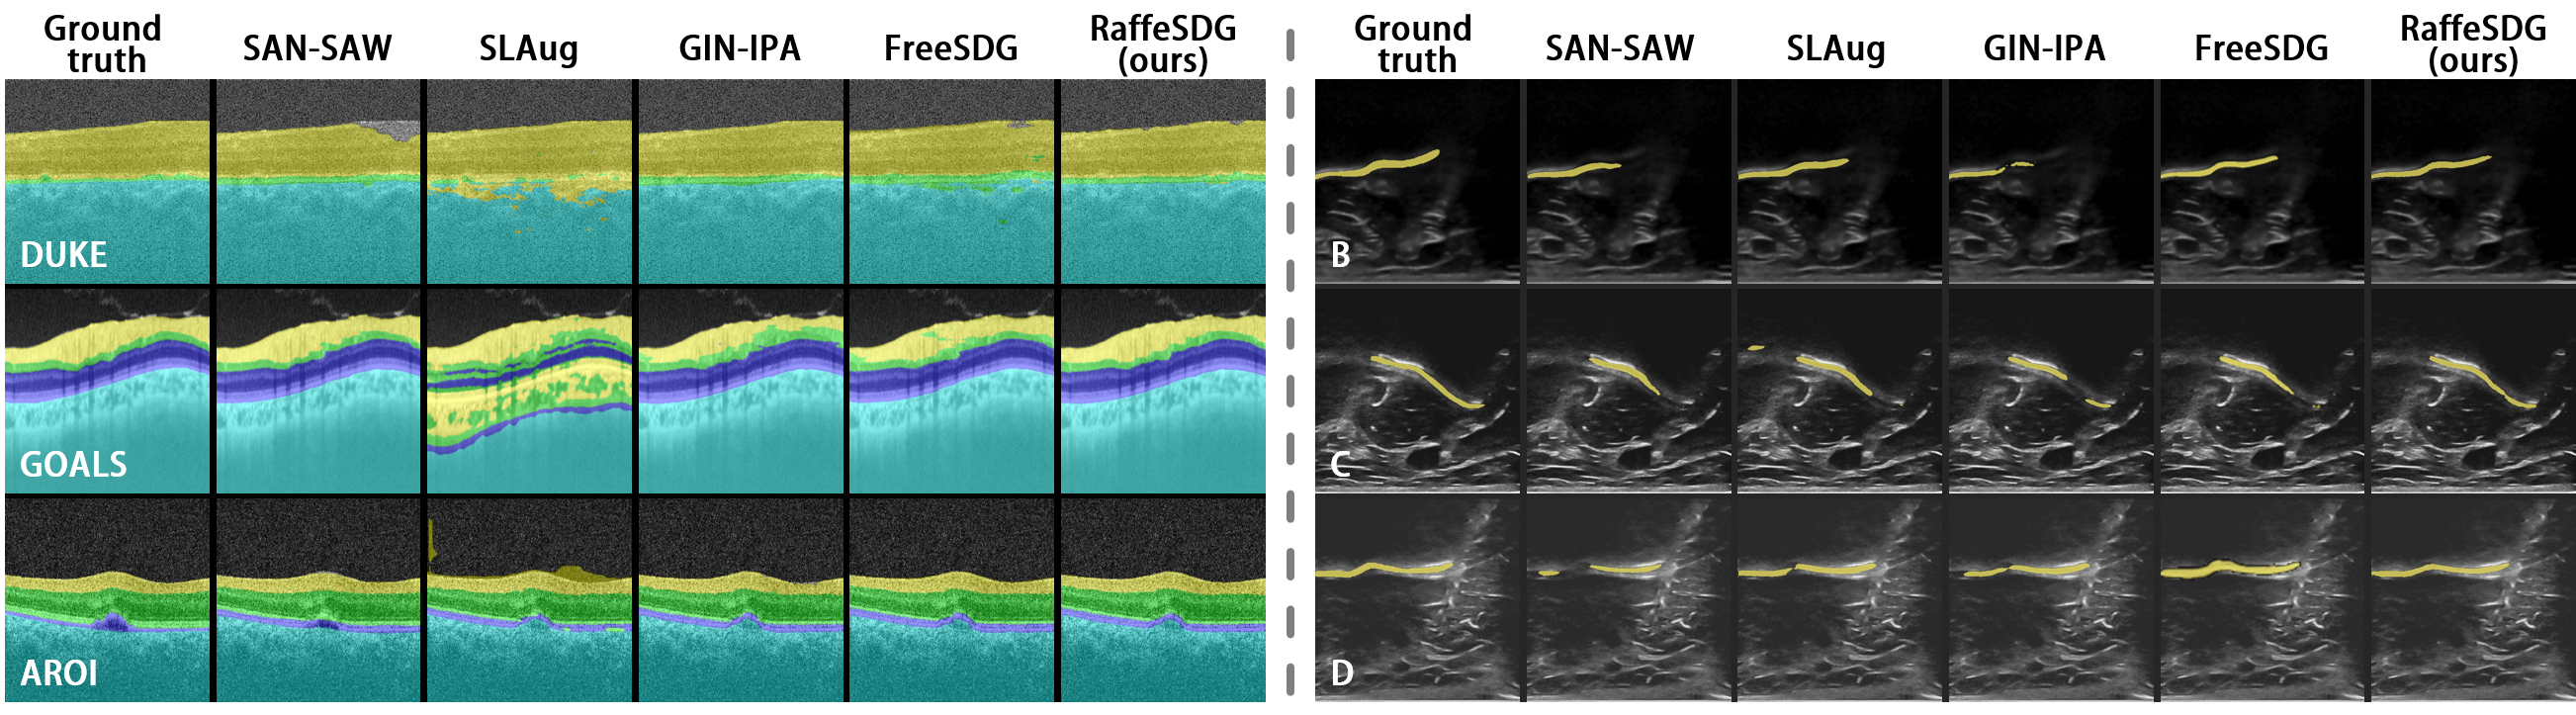

Refer to caption

Figure 9: Visualized comparisons with SOTA SDG algorithms for OCT and ultrasound segmentation.

TABLE VI: Comparisons of OCT and ultrasound segmentation. The top three results are indicated in red, magenta, and blue.

SDG algorithms OCT DICE Ultrasound DICE

DUKE GOALS AROI Avg. B C D Avg.

SAN-SAW [16] 0.860 0.613 0.771 0.748 0.735 0.825 0.750 0.770

SLAug [13] 0.483 0.316 0.458 0.419 0.745 0.830 0.765 0.780

GIN-IPA [14] 0.952 0.569 0.703 0.743 0.715 0.834 0.781 0.777

FreeSDG [15] 0.885 0.565 0.760 0.736 0.750 0.826 0.759 0.778

RaffeSDG(ours) 0.901 0.579 0.778 0.753 0.766 0.847 0.793 0.802

Comparisons of out-of-domain inference for OCT and ultrasound image segmentation were also performed to validate the effectiveness of RaffeSDG. Visualized and quantitative summaries of these comparisons are respectively presented in Fig. 9 and Table VI.

Considering that SAN-SAW [16] and GIN-IPA [14] employ specific designs for multi-category labels, it is understandable that they achieve remarkable performance in the retina layer segmentation of OCT, as expressed in Table VI. However, the nature of OCT and ultrasound data poses limitations for RaffeSDG. Unlike colorful fundus data obtained through visible light, OCT and ultrasound utilize wave propagation characteristics to capture images of internal structures, resulting in an inherently grayscale appearance. Consequently, OCT and ultrasound do not lend themselves well to the advantages of RaffeSDG, as illustrated in Fig. 9. Fortunately, despite these constraints, RaffeSDG still manages to achieve decent results, highlighting its versatility in medical image segmentation.